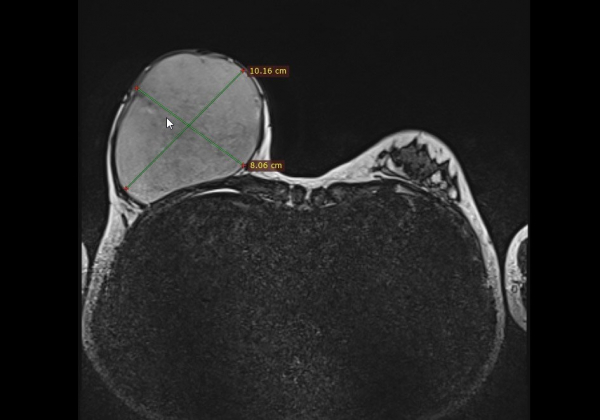

«Перед операцією було виконали МРТ-дослідження для детальної оцінки пухлини та планування втручання. Оперативне втручання пройшло успішно — хірурги та анестезіологи нашого закладу видалили пухлину розмірами 10х8х8 см і вагою 720 г.

За результатами ультразвукового дослідження (УЗД) було виявлено велике об’ємне утворення розмірами 9х8 см, яке відтискало тканини залози вгору та назовні. Для уточнення діагнозу була проведена трепан-біопсія. Гістологічне дослідження підтвердило наявність рідкісної пухлини — «Гігантської ювенільної фіброаденоми», яка становить лише 0,5-2% від усіх новоутворень грудної залози та переважно зустрічається у молодих пацієнток.